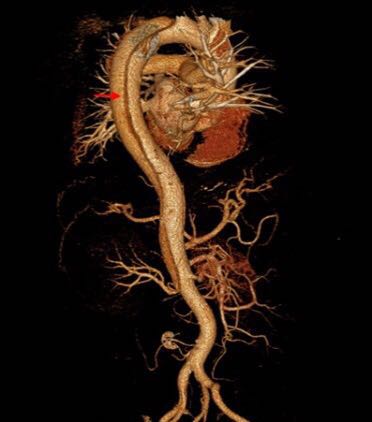

2、增强CT:常用手段。安全、简单、准确,有诊断和术前评估价值。

5、数字减影血管造影(DSA)是诊断主动脉夹层的有效手段,但价格昂贵。